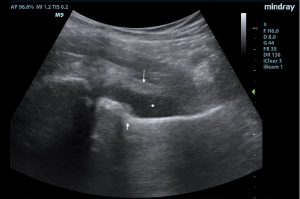

Initial ED course involved IV hydration, analgesia, and labs demonstrating ongoing leukocytosis with left shift, normal coagulation studies, and normal liver and renal function. Urine was sent for N. Gonorrhoeae and C. Trachomatis nucleic acid amplification tests. POCUS examination of bilateral hips revealed a 10 mm fluid collection anterior to the left femoral neck consistent with a hip effusion. Orthopedic surgery was consulted and requested an arthrocentesis, a procedure typically performed by an IR team at this institution, requiring time for transport, team organization, and room set-up. The EM team therefore elected to perform a POCUS-guided arthrocentesis.

With a linear array transducer positioned transversely over the inguinal region, the location of the femoral neurovascular bundle was marked using a surgical pen. The transducer was then rotated into a sagittal oblique position to visualize the hip effusion, and depth was measured to determine appropriate needle length. A low-frequency curvilinear probe was also briefly used to optimize visualization and to compare bilateral hips (Figures 1 and 2).

Under POCUS guidance, a 22-gauge 3.5-inch spinal needle was inserted distal to the long axis of the linear transducer and lateral to the femoral vessels. The needle was advanced in-plane to enter the anterior synovial recess and 10 ml of blood-tinged, purulent fluid was aspirated. There were no procedural complications and the patient had immediate resolution of pain with improved range of motion.